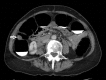

Schwannomas are peripheral nerve sheath tumours that can present as a rare tumour of GI tract, and even more uncommonly within the colon. We present a case of colonic schwannoma in an asymptomatic patient identified on surveillance colonoscopy. The tumour is of mesenchymal origin and is often challenging to diagnose prior to surgical resection. Endoscopy usually fails to provide adequate sample and diagnosis is usually confirmed on immunohistochemistry.